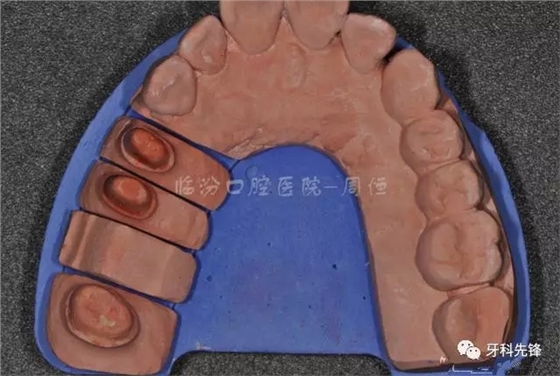

圖13牙體預(yù)備模型照

640.webp (17).jpg